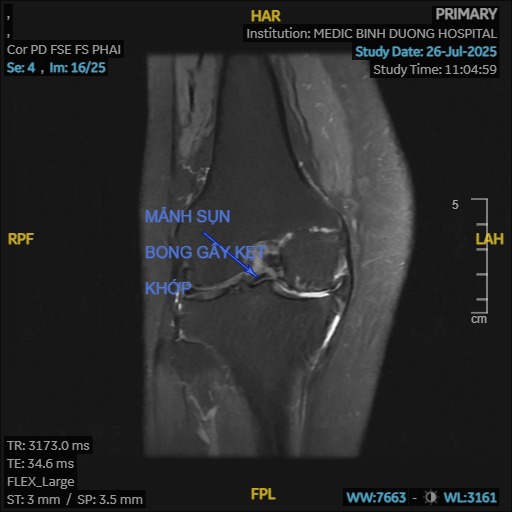

- Khớp phát ra tiếng kêu: Khi cử động khớp gối có thể nghe thấy tiếng lục khục, lạo xạo do bề mặt sụn khớp bị gồ ghề.

- Chấn thương: Các chấn thương cũ ở khớp gối (gãy xương, rách sụn chêm, tổn thương dây chằng) có thể làm thay đổi cấu trúc khớp và đẩy nhanh quá trình thoái hóa.